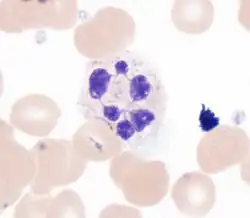

В мазках крови нейтрофилы имеют диаметр от 12 до 15 мкм. В суспензии человеческие нейтрофилы достигают 7—9 мкм в диаметре[15]. Неактивированные нейтрофилы, плавающие в кровотоке, имеют сферическую форму; после активации форма нейтрофилов меняется, становится амёбоидной, появляются псевдоподии, с помощью которых нейтрофилы могут захватывать антигены[16].

Подобно базофилам и эозинофилам, зрелые нейтрофилы имеют дольчатое клеточное ядро из 2—5 сегментов, соединённых тонкими перемычками. У некоторых животных ядро зрелых нейтрофилов не имеет отчётливой сегментации[14]. По мере созревания нейтрофила ядрышко исчезает (исчезновение ядрышка происходит лишь у некоторых типов дифференцированных клеток, имеющих ядро). Центр ядра составляет эухроматин, а гетерохроматин сосредоточен на периферии. У женщин некоторые нейтрофилы несут инактивированную X-хромосому в виде тельца Барра, которое выглядит как придаток в виде барабанной палочки у одного из сегментов ядра[19][20]. Поскольку промоторы многих генов в ядре нейтрофила недоступны для дифференцировочных факторов, экспрессия генов и возможность к биосинтезу макромолекул у нейтрофилов ограничены. Тем не менее нейтрофилы всё же сохраняют способность к биосинтезу, хотя и ограниченному. У незрелых палочкоядерных нейтрофилов ядро не подразделено на сегменты, хотя содержит уплотнённый хроматин[21].

Аппарат Гольджи, как правило, слабо развит, митохондрии и рибосомы редки, шероховатый эндоплазматический ретикулум (ЭПР) отсутствует. В цитоплазме имеется от 50 до 200 гранул, из которых приблизительно 10—20 % (по некоторым оценкам, до трети) составляют азурофильные гранулы[22], оставшиеся 80—90 % приходится на специфические гранулы. Азурофильные гранулы окружены одинарной мембраной, они более крупные, чем специфические, и имеют диаметр около 0,4 мкм, окрашиваются в фиолетово-красный цвет. Они представляют собой первичные лизосомы, содержат электронно-плотную сердцевину и ферменты, активные при низких значениях pH: кислую фосфатазу, β-глюкуронидазу, миелопероксидазу, которая продуцирует из перекиси водорода молекулярный кислород, имеющий антибактериальные свойства, α-фукозидазу, 5’-нуклеотидазу, арилсульфатазу, β-галактозидазу, α-маннозидазу, N-ацетилглюкозаминидазу, лизоцим, нейтральные протеазы (катепсин G, эластаза, коллагеназа, азуроцидин). Кроме того, азурофильные гранулы содержат антимикробные пептиды из числа дефензинов[20], кателицидинов, гранулофизин, лактоферрин, кислые гликозаминогликаны. Поскольку в ходе дифференцировки нейтрофилов в костном мозге азурофильные гранулы появляются раньше специфических, их также называют первичными гранулами[23]. Молекулярные маркеры азурофильных гранул — миелопероксидаза и мембранная молекула CD63[24].